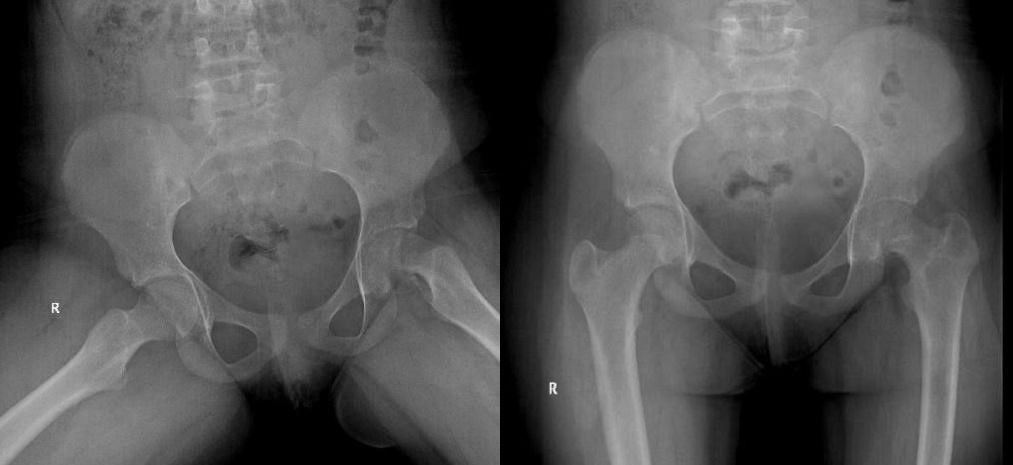

Se solicita una radiografía de caderas, observándose en el lado izquierdo un desplazamiento inferior de la epífisis respecto a la metáfisis (Fig. 1 y 2) no estando alterada la congruencia articular, y con cadera derecha normal.

Figuras 1 y 2. Desplazamiento inferior de la epífisis respecto a la metáfisis

Figura 1. Desplazamiento inferior de la epífisis respecto a la metáfisis